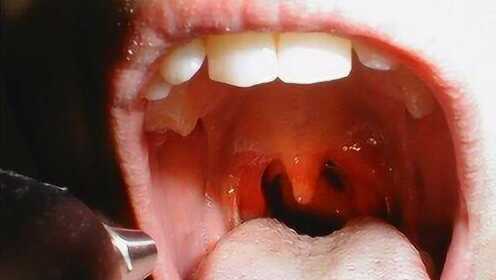

慢性咽炎概述

慢性咽炎是一種常見的喉部疾病,主要表現(xiàn)為咽部不適、干燥、瘙癢、疼痛等癥狀,由于長期受到刺激或感染,咽部黏膜出現(xiàn)慢性炎癥表現(xiàn),慢性咽炎雖然不是嚴重疾病,但癥狀反復發(fā)作,嚴重影響患者的生活質(zhì)量。